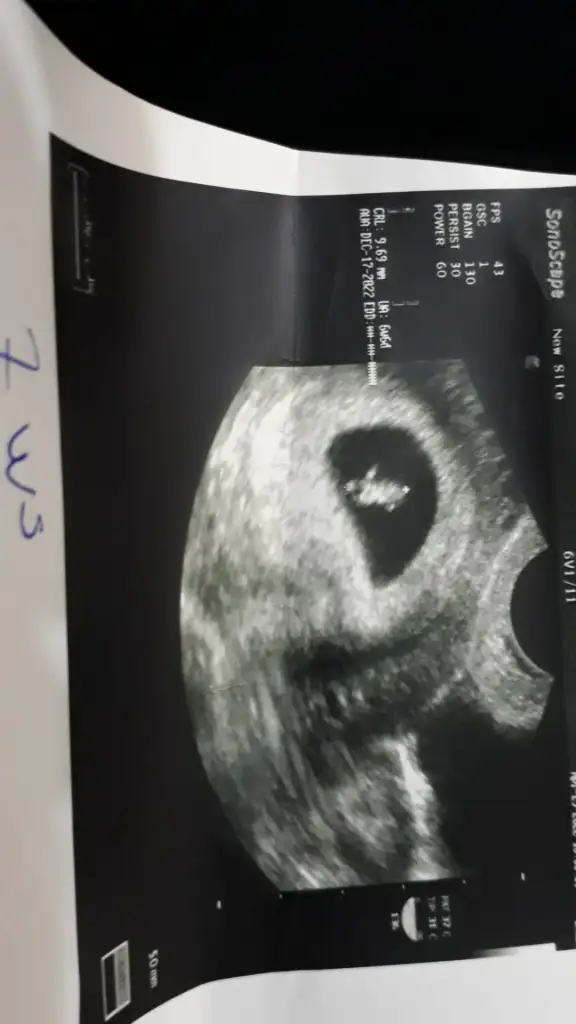

Yine geldim buralara 12. hafta karın ultrasonundan 😅

• 20220506_160435.webp

20220506_160435.webp

21,6 KB · Görüntüleme: 57